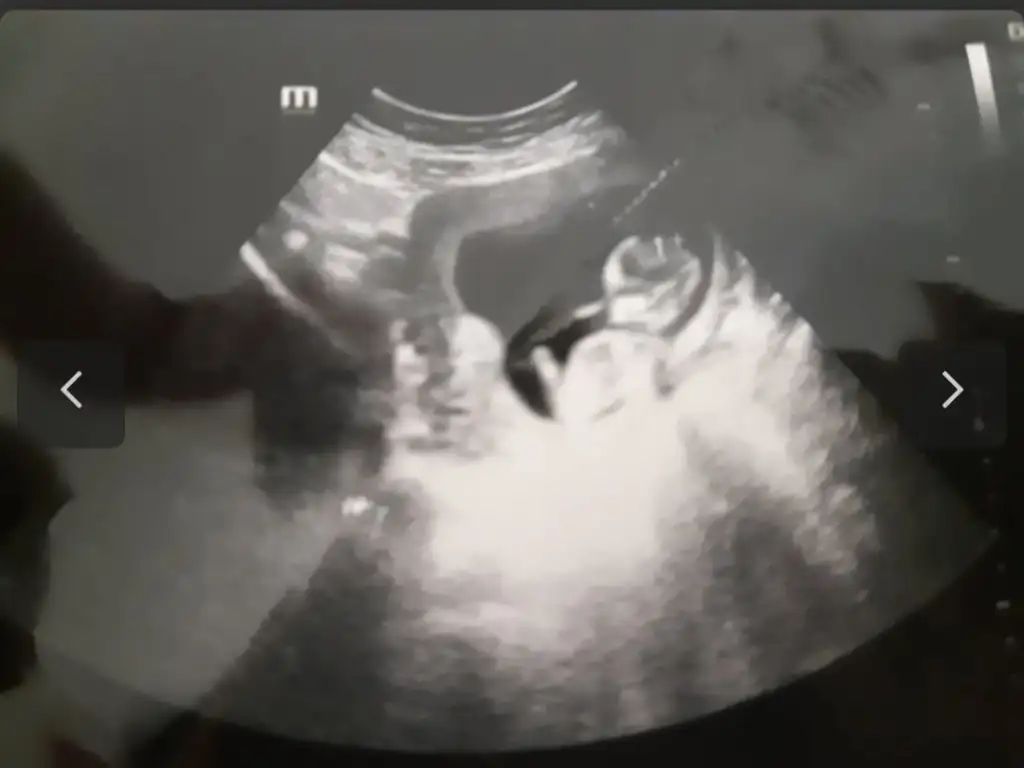

prenses gibi12+6 karından ultrason

Bana bakarmisiniz rica etsem9 hafta 2 günlük karından bakildi

Bana da bakarmisiniz 9+2 karindankarındansa prenses gibi